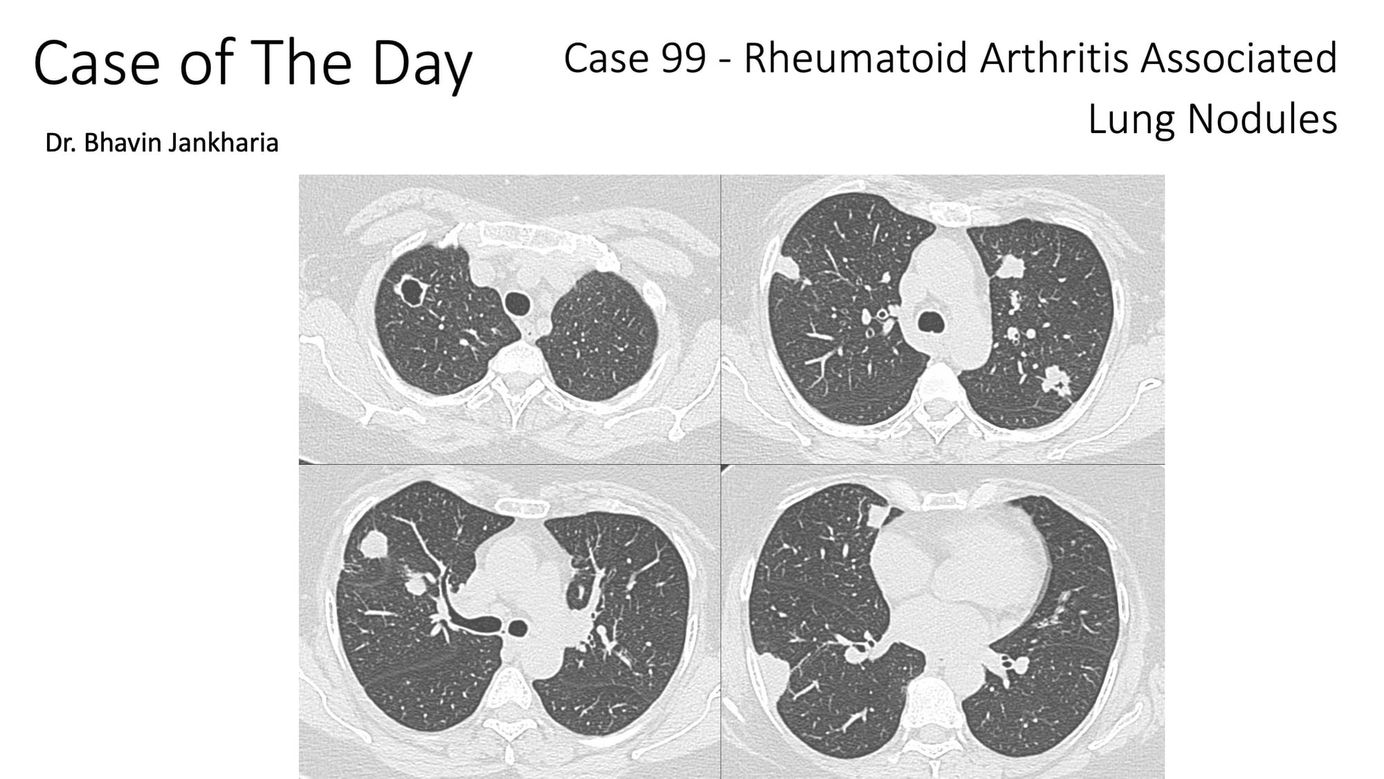

Case of the Day - 099 - Rheumatoid Arthritis Associated Lung Nodules Paid Members Public

When multiple nodules are seen in a patient with RA, it is necessary to rule out infection, neoplasm and associated vasculitis before labeling them as rheumatoid nodules